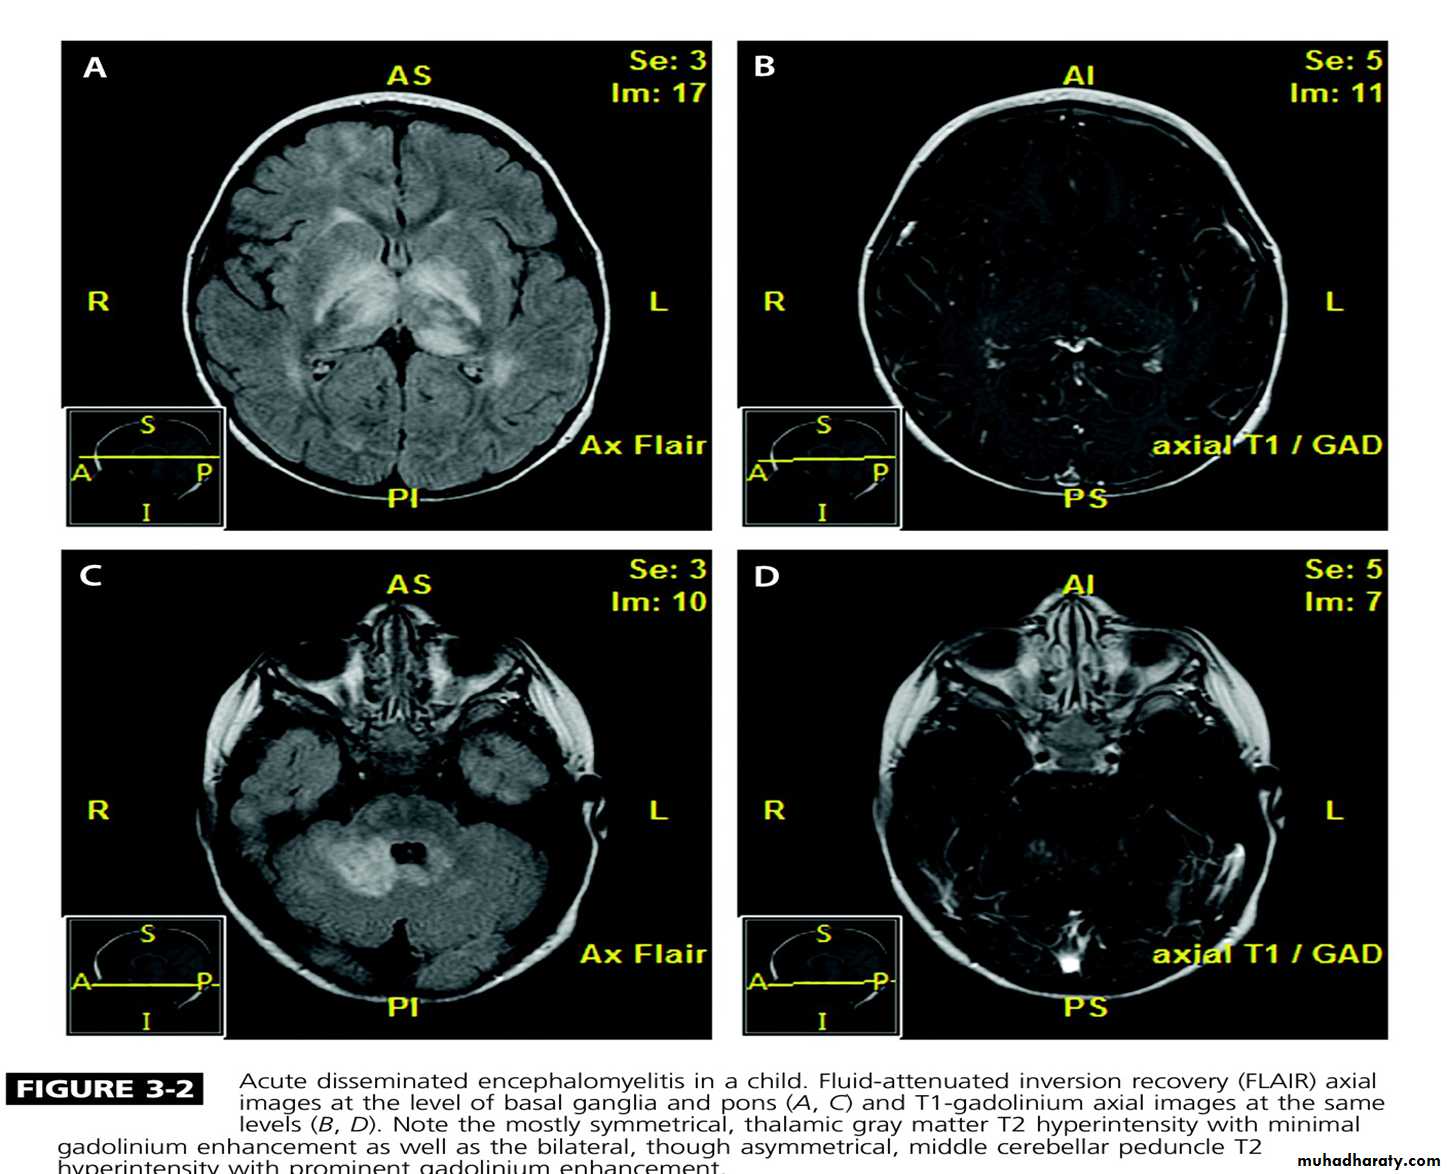

Acute disseminated encephalomyelitis

This is an acute monophasic demyelinating condition in which there are areas of perivenous demyelination widely disseminated throughout the brain and spinal cord. The illness may apparently arise spontaneously but often occurs a week or so after a viral infection, especially measles and chickenpox, or following vaccination, suggesting that it is immunologically mediated.

Headache, vomiting, pyrexia, confusion and meningism may be presenting features, often with focal or multi focal brain and spinal cord signs. Seizures or coma may occur.

MRI shows multiple high-signal areas in a pattern similar to that of MS, although often with large confluent areas of abnormality. The CSF may be normal or show an increase in protein and lymphocytes (usually 200 cells/L) . The clinical picture may be very similar to a first relapse of MS.Management: